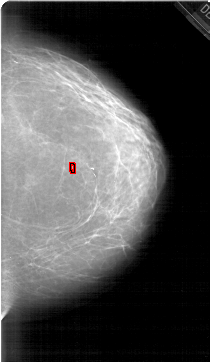

FILE: A_1452_1.RIGHT_MLO.OVERLAY

TOTAL_ABNORMALITIES 1

ABNORMALITY 1

LESION_TYPE CALCIFICATION TYPE PLEOMORPHIC DISTRIBUTION CLUSTERED

ASSESSMENT 4

SUBTLETY 4

PATHOLOGY BENIGN

TOTAL_OUTLINES 1

BOUNDARY